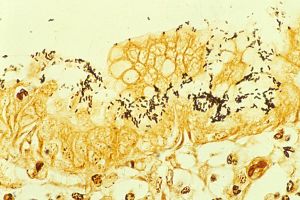

Immunohistochemical detection of Helicobacter (1) histopatholgy.jpg

Immunohistochemical staining of H. pylori from a gastric biopsy